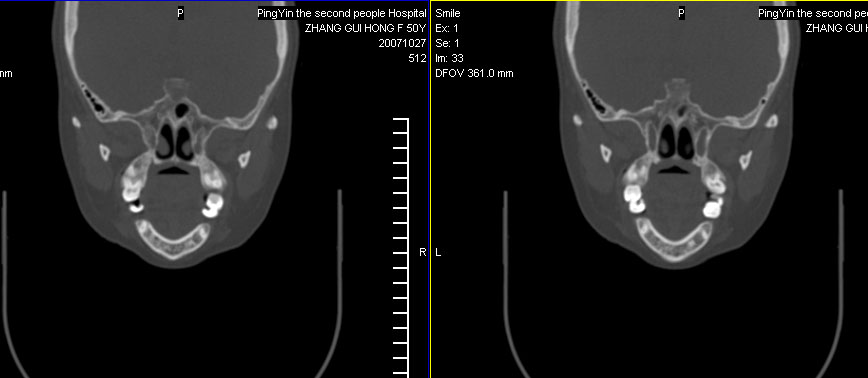

标题: CT10219:蝶鞍区有无异常?

女。50岁.头疼恶心半月余.双上颌窦区压疼明显,曾有高血压.现基本控制.

有问题,双侧侧脑室扩大,感觉鞍区有肿块,建议增强扫描.

感觉鞍区异常,建议增强扫描或mri!

平扫未见异常,建议直接mri吧。